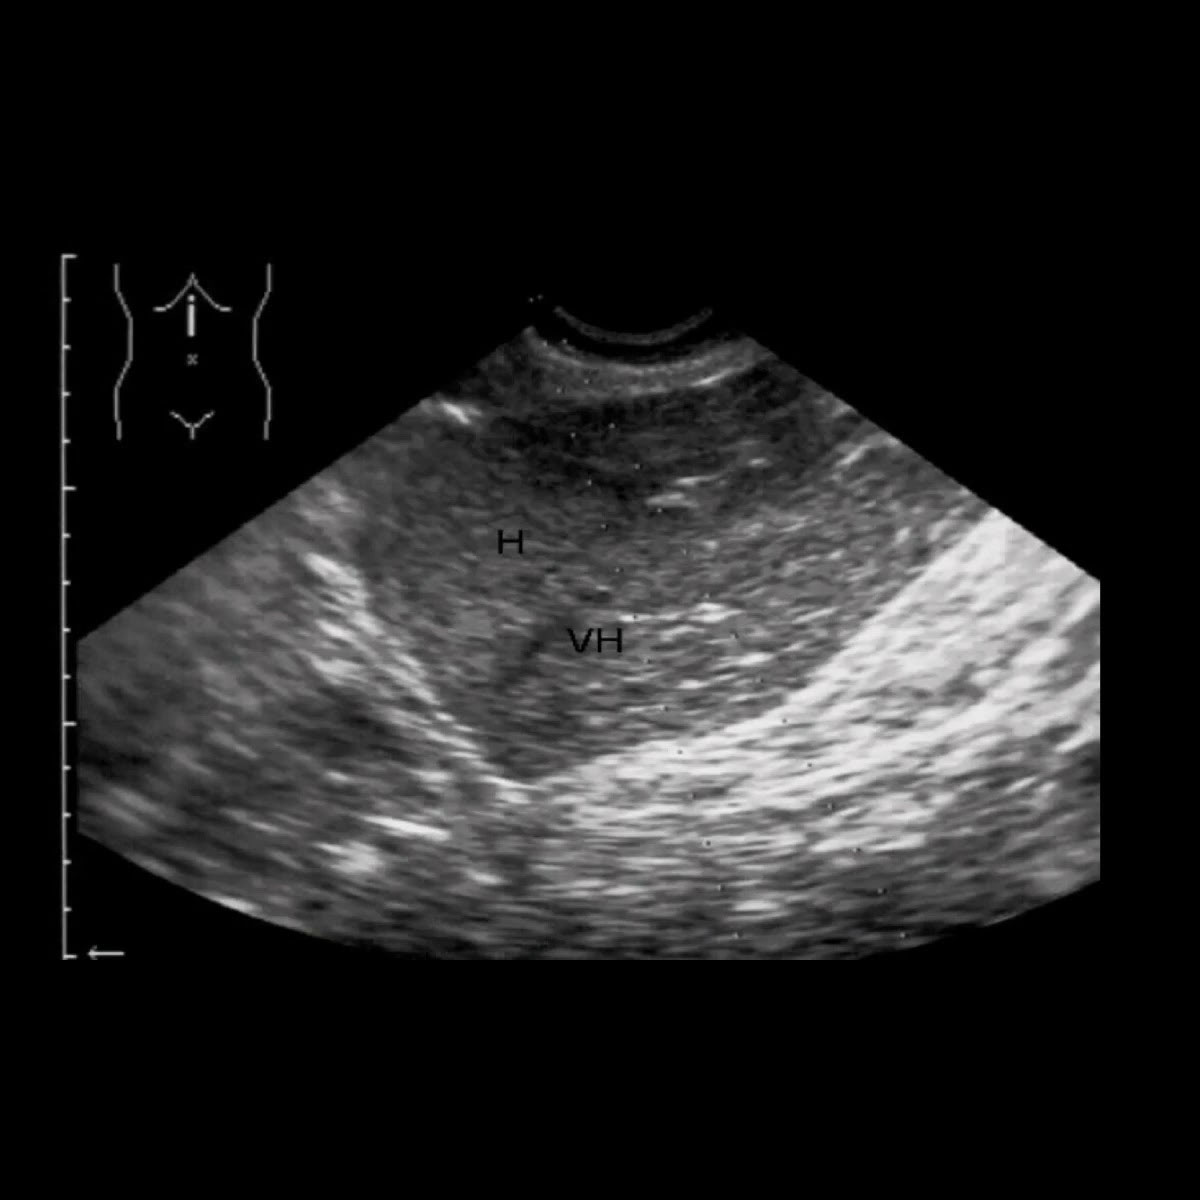

Ultrasound images • Liver autoimmune hepatitis, Bmode & color Autoimmune Hepatitis Usg autoimmune hepatitis ( aih ) (plural: autoimmune hepatitis can present in a variety of ways from an asymptomatic elevation of liver enzymes noted on. management of autoimmune hepatitis. autoimmune hepatitis is a generally progressive, sometimes fluctuating chronic hepatitis of unknown cause that. ultrasound findings in autoimmune hepatitis (aih) have not been reported systematically so far.. Autoimmune Hepatitis Usg.

Liver Atlas Case 414 Hepatitis, acute Autoimmune Hepatitis Usg ultrasound findings in autoimmune hepatitis (aih) have not been reported systematically so far. Autoimmune hepatitides) is a rare type of chronic hepatitis, classified as type 1 or type 2. management of autoimmune hepatitis. autoimmune hepatitis is associated with varied clinical presentations and natural history, as well as somewhat. It may eventually lead to. autoimmune hepatitis can. Autoimmune Hepatitis Usg.

Autoimmune hepatitis Image Autoimmune Hepatitis Usg autoimmune hepatitis ( aih ) (plural: ultrasound findings in autoimmune hepatitis (aih) have not been reported systematically so far. Autoimmune hepatitides) is a rare type of chronic hepatitis, classified as type 1 or type 2. autoimmune hepatitis can present in a variety of ways from an asymptomatic elevation of liver enzymes noted on. management of autoimmune. Autoimmune Hepatitis Usg.